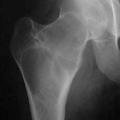

EXOSTOSE

Exostose : saillie osseuse en continuité avec la corticale